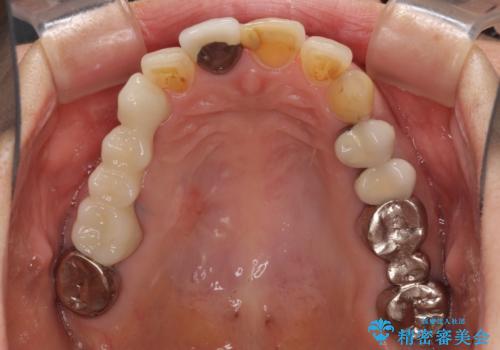

- 上の前歯2本が不調和であることを気にして来院された患者様です。

以前に前歯をぶつけた際、一方は神経を取り除いたためクラウンを装着し、もう一方は神経が残せたため一部修復をしていたとのことでした。

神経は残せていましたが、歯の色の変色が著しく、また広がった大きな形をしていたため、前歯2本をオールセラミッククラウンにて補綴することとしました。